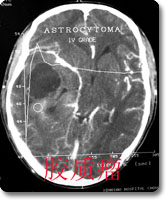

中枢神经影像诊断是本科室的特色、强项诊断之一,尤其是现代影像学诊断,如CT、MRI等,是西南地区最早开展此项工作的单位,积累了丰富的临床经验,有较高的诊断水平。如对脑肿瘤的影像学表现和肿瘤分子生物学基础的对照研究、脑血管病的诊断和介入治疗等在国内处于领先地位。